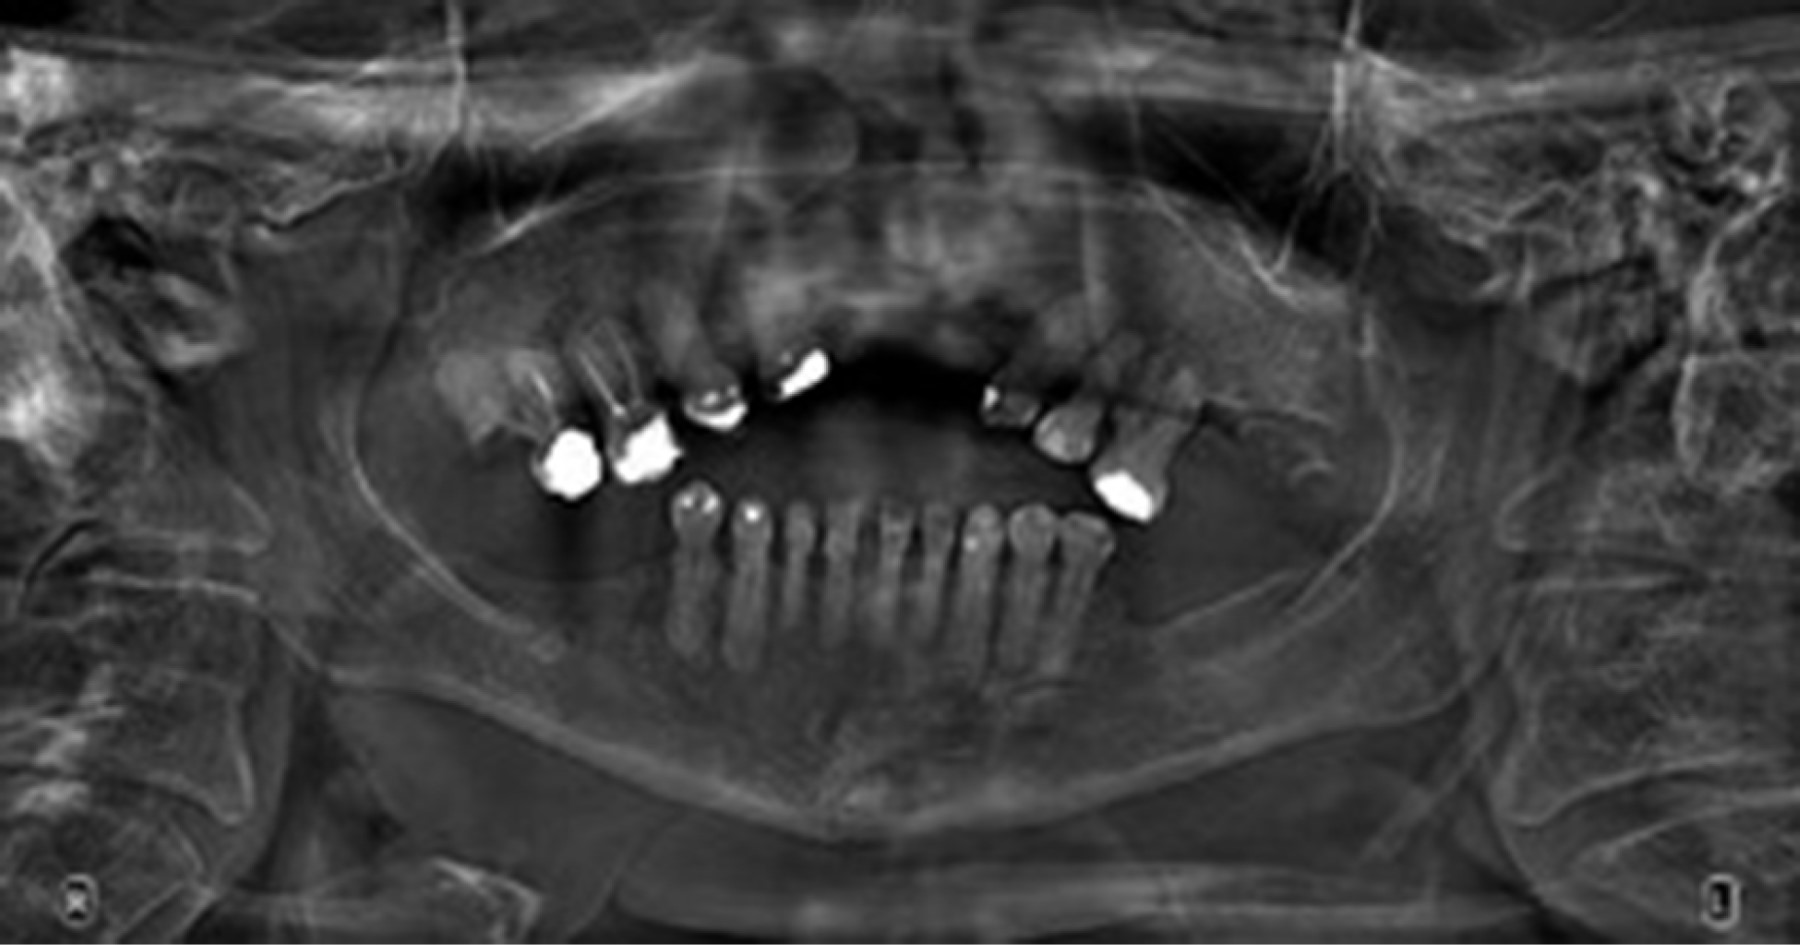

Se procede a realizar el diagnóstico intraoral de la paciente con el apoyo de radiografías periapicales y ortopantomografía, así como modelos de yeso. Valoración por las especialidades de periodoncia, cirugía, prótesis y endodoncia.

Radiográficamente se observó anodoncia parcial, caries y restauraciones defectuosas/mal adaptadas, pérdida de hueso horizontal y/o vertical en todos los sextantes, cráteres óseos, paladar hendido, hipercementosis en todos los dientes, raíces enanas, fracturas coronarias, seno y membrana maxilar pequeña, alteración de la articulación temporomandibular y restos radiculares (Figuras 2 y 3).

Figura 2